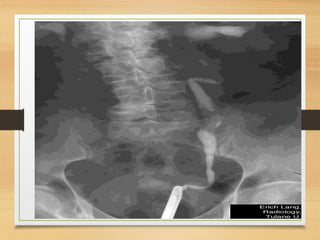

Radiological

• KUB

CASE 2

• A 35-year-old man presents to the emergency

department with intermittent right loin to groin pain

and visible hematuria. He had history of passing

stones . What is the likely cause?